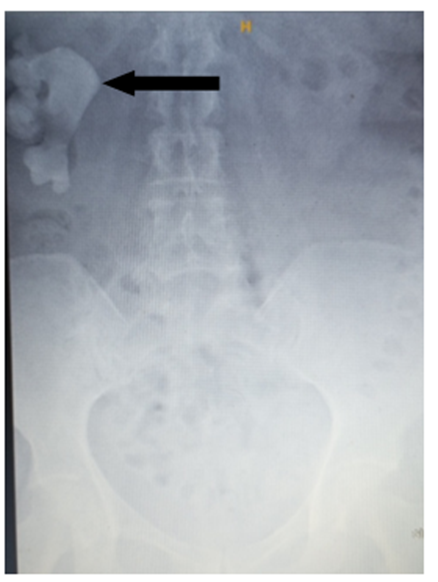

Plain abdominal X-ray (Figure. 1) showed right kidney (RK) enlargement with a large staghorn calculus.

Figure 1: Plain abdominal X-ray: Right kidney enlargementwith a large staghorn calculus (black arrows).